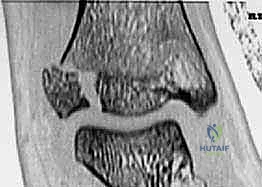

كسور كاحل الأطفال: دليلك الشامل للعلاج الجراحي المتقن في صنعاء مع الأستاذ الدكتور محمد هطيف

دليلك الشامل لكسور كاحل الأطفال وعلاجها الجراحي المتقن في صنعاء. تعرف على التشخيص، الخطوات الجراحية، والتعافي تحت إشراف الأستاذ الدكتور محم…